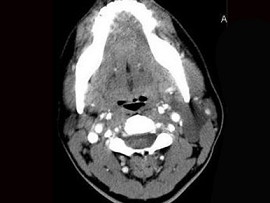

6.CT檢查結果見下圖,本患者應考慮為  (    )

正確答案:6.C;7.E